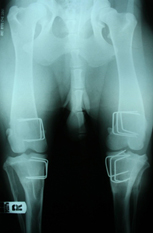

- Вальгусная деформация тазовых конечностей (genu valgum)

Вальгусная деформация тазовых конечностей у собак обусловлена увеличением шеечно-диафизарного угла бедренной кости, что приводит к выраженной деформации бедренной и большеберцовой кости, что в совокупности дает Х — образную постановку тазовых конечностей. Для постановки данного диагноза необходимо выполнить рентгенограммы таза в первой позиции.

Рис. 4. Рентгенограммы таза в первой позиции. Увеличение шеечно-диафизарного угла правого и левого ТБС (а). Х-образная деформация обеих тазовых конечностей (б). Макрофото. Х – образные тазовые конечности (в).

Для исправления вальгусной деформации тазовых конечностей животному выполняли межвертельную остеотомию бедренной кости и клиновидную остеотомию большеберцовой кости. Операцию на второй конечности проводили с интервалом 1 мес. Для фиксации отломков использовали специальные импланты. Снятие пластин не проводили по желанию владельцев.

Рис. 5. Рентгенограмма таза в первой позиции, после выполнения поэтапной межвертельной остеотомии правой и левой бедренной кости и клиновидной остеотомии правой и левой большеберцовой кости (а). Животное через 1,5 года после операций (б).